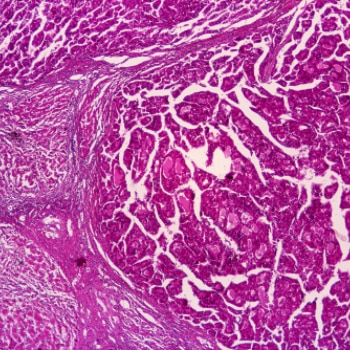

Le cancer est actuellement la deuxième cause de mortalité dans le monde, malgré les immenses progrès accomplis ces 30 dernières années par les chercheurs et spécialistes en oncologie du monde entier.

Pierre Fabre est un acteur de l’oncologie depuis 1978 et dispose d’une solide expertise dans les cancers du poumon, du sein et de la vessie et plus récemment dans le mélanome.

Aujourd’hui, le Groupe fait de la recherche en oncologie sa priorité en matière de R&D.

Nous profitons d’une approche globale centrée sur le patient pour renforcer notre compréhension scientifique du microenvironnement tumoral et notre capacité à fournir des produits biologiques de haute qualité basés sur de multiples plateformes technologiques telles que les anticorps monoclonaux et les immunoconjugués.

Les travaux de recherche menés par nos experts couvrent des domaines dans lesquels il existe des attentes médicales majeures: cancers de la peau, du côlon, du sein et du poumon.